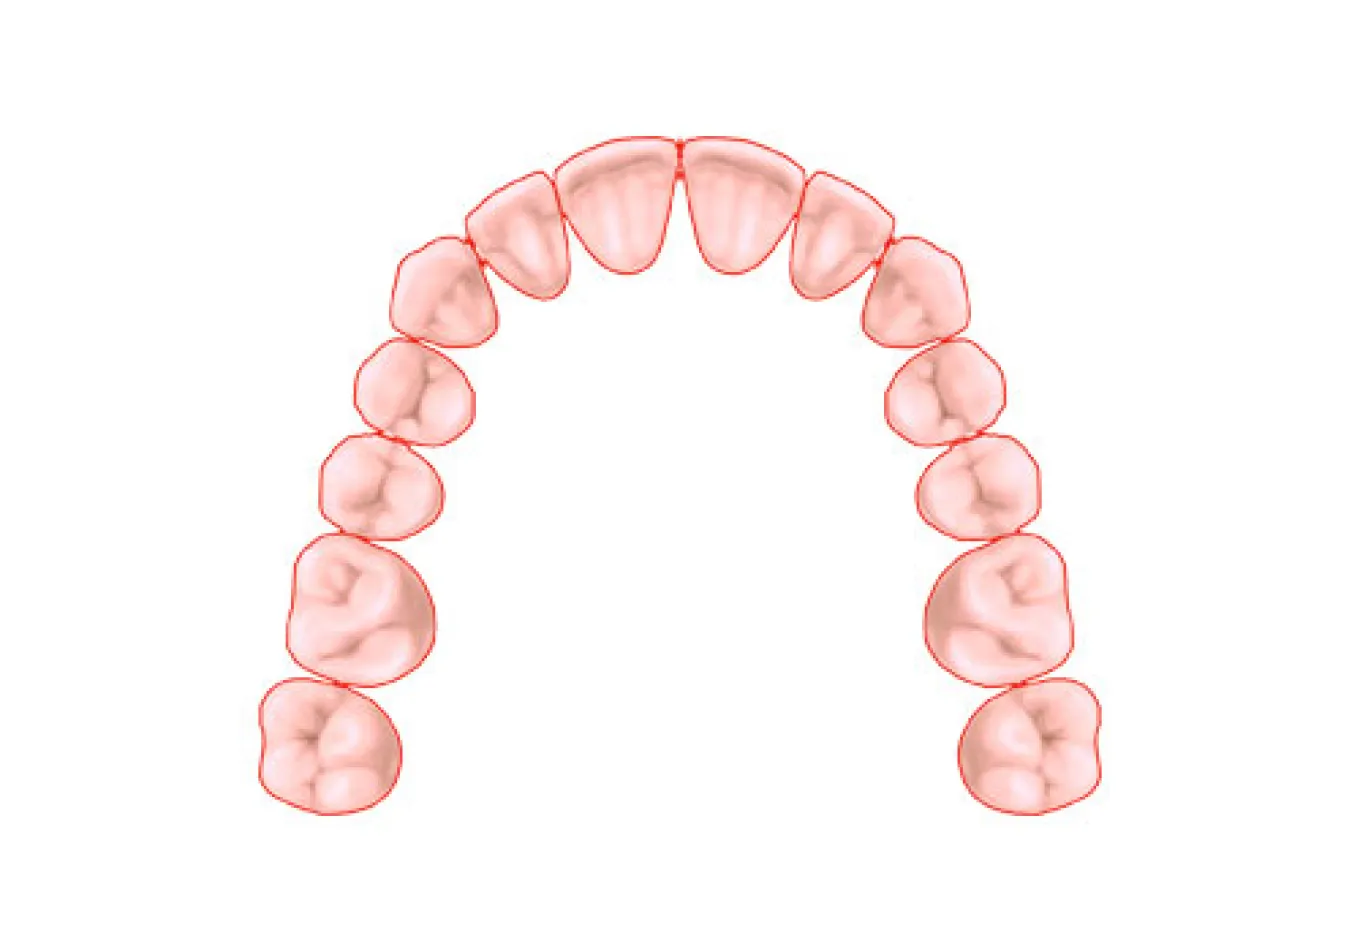

インプラント(implant)とは、“植え込む”という意味の英語です。インプラントの仕組みは、歯を失ってポッカリ穴が開いてしまった部分の歯龎骨へ穴を開け、インプラント体(フィクスチャー)と呼ばれる金属製の人工歯根(インプラント体)を埋め込み、その上に人工の歯を被せるしくみです。 歯龎の骨にしっかりとインプラント体を固定する事により、浮かない・ずれない・しっかりとした噛み心地を実現する事が出来ます。 人は永久歯を失うと、残念ながら二度と生え変わってきません。そのため、今までは『義歯(入れ歯)』『ブリッジ』などを用いて食事や会話 を取り戻すといった方法でしか、その部分を補う事はできませんでした。 しかし、『義歯(入れ歯)』だと固いものがうまく噛めない、発音がおかしい、また長く使っている間に合わなくなってガタガタする場合があります。 このように、歯を失ってお悩みの方にご提供することができる、最新歯科医療の治療方法『インプラント治療(人工歯根)」です。 歯を抜けたままにして放置しておくと、お口の中には様々な影響が出てきます。奥歯の下の歯が1本抜けた場合、まずこれまでその歯と噛み合っていた上の歯が下に伸びてきます。また、両隣の歯が抜けた歯の方向に倒れてきて、さらにはそこにプラークがたまりやすくなってしまいます。結果として、虫歯や歯周病などが誤発されることがあります。歯はかなり緬密に全体のバランスの中で成り立っているものなので、例え1本の欠損の場合でも、そのままにしておくことはお勧めできません。 機能的な影響 見た目上の影響 生活上の影響 取り外す入れ歯が嫌な方、取り外す入れ歯の清掃が面倒くさいと感じる方 入れ歯は食事のたびにお口から取って清掃しなくてはなりません。清掃が不十分だと歯周病の原因となります。お悩みの方は一度、ご相談下さい。 入れ歯が合わない方、何度も入れ歯をつくり直している方 入れ歯は歯肉を圧迫するので、歯肉がやせていきます。歯肉がやせると入れ歯との間に隙間ができ、密着しにくくなりお食事中などに外れる場合があります。 入れ歯で発音しにくい(話しにくい)方 入れ歯を使い始めてすぐは、発音のしづらさを感じます。人前で話す機会の多い方や英語を話す方は入れ歯により発音が悪くなります。特に、 楽器の演奏をされる方で前歯を失った場合には、インプラント治療が非常にお勧めです。 思いっきり笑ったり、歯を見せて話ができない方、入れ歯のバネが気になっている方 会話や食事の際など、お口をあけた時に入れ歯のバネが見えてしまう場合があります。入れ歯のバネが気になっている方は当院にご相談下さい。 口臭が気になる方 最近、口臭が原因で来院される患者様が増えています。実際に当院では口臭があると診断された患者様のほとんどの方が歯周病に侵されます。歯周病に侵され、残念ながら歯を失うことになった場合には、インプラント治療を勧められることがあります。 昔食べられていたものが噛めない方、左右片方でしかものが噛めない方 入れ歯は天然歯の1/3程度しか噛む力がありません。総入れ歯の場合は硬いものを噛むときに痛みを覚えます。昔の「歯」のようにしっかり噛 んで食事をしたいとお考えの方は一度、ご相談下さい。 自分の歯のように見た目をきれいにしたい方 インプラントは、天然歯とほとんどかわらない「機能性」「審美性」をもっています。自分の歯のように見た目を綺麗にしたいとお考えの方 は一度お問い合わせください。 健康な歯は、これからもできる限り残したい方 インプラント治療なら、隣の歯(まわりの健康な歯)を傷つけることなく欠損した歯だけを治療することが可能です。健康な歯を出来るだけ 残したいとお考えの方は当院までお問い合わせください。 旅行やスポーツを積極的に楽しみたい方 旅行先での美味しいものを存分に味わいたい、スポーツをする際、歯に力を入れたい、積極的に楽しみたいとお考えの方には、インプラント 治療がお勧めです。一度、当院にお問い合わせください。一つでもチェックした方はまず、当院へご相談下さい。 しっかりと噛める インプラントはあごの骨の中に埋め込まれ、しっかりと固定されますので、入れ歯とは違い、しっかりとした噛み心地が得られるのが大きな魅力です。しっかりと噛めるというのは、消化の面で良いのはもちろんですが、その他にも認知症の予防や、体の運動能力の向上にも役立つことがわかっており、若々しさを保つ上でも役立ちます。 見た目が自然 インプラントは人工歯根をあごの骨に埋め込み、その上に被せ物をする治療ですが、実際に表から見える部分というのは被せ物の部分だけです。被せ物は主に周囲の歯に似せたセラミックを入れますので、まるでご自分の歯のように見えます。 違和感がなく快適 インプラントの人工歯根は骨と結合して一体化し、まるで体の一部のような感じになります。一方、取り外し式の入れ歯の場合、歯茎の上に乗っているため、違和感に悩まされる方も少なくありません。 残った歯を長持ちさせてくれる インプラントは、単独で歯を立てられる治療法ですので、他の治療法と違い、周囲の歯にダメージを与えることがありません。例えばブリッジの場合、失った歯の両隣の歯をたくさん削って被せなければなりませんし、入れ歯の場合だと、残っている歯に金具をかけて入れ歯を支えなければなりません。このような周囲の歯へのダメージが徐々に歯を弱らせてしまうことにつながっていき、最終的には歯の寿命を短くしてしまいます。単独で歯をおぎなうことのできるインプラントは、歯を全体的に健康に保ってくれる治療法だと言えるでしょう。 お手入れが楽 インプラントは、基本的にご自分の歯を磨くようにお手入れをします。一方、入れ歯の場合は取り外して入れ歯とご自分の歯を別々に磨く必要がありますし、ブリッジの場合には、つなぎの部分などの形が複雑で、隅々まで磨くのが大変です。 あごの骨がやせにくい インプラントとあごの骨はしっかりと結合していますので、噛んだ刺激は直接骨に伝わります。あごの骨というのは噛む刺激を受けないとだんだんやせてしまいます。そのため、入れ歯やブリッジの場合には徐々に骨がやせていきます。インプラントの場合には常に噛む刺激が伝わるため、骨の高さが維持されてお顔の張りも保たれることになり、若々しい見た目を維持することができます。 保険適用にならない 通常、インプラントは保険が適用されません。そのため、治療費は100%自己負担となりますので高額になってしまいます。 手術を受けなければならない インプラントは人工歯根をあごの骨に埋める手術が必要です。手術の侵襲の程度は抜歯程度のものが多いですが、やはり外科的な処置が必要になります。 治療期間が長くかかる インプラントは他の治療法に比べて治療期間が長くかかります。それはインプラントがあごの骨と結合するまでじっくりと待たなければならないためです。通常、下あごの場合3ヶ月程度、上あごの場合6ヶ月程度ほど治療期間がかかりますが、骨が少ない場合には骨を作る治療が必要となりますので、さらに数ヶ月かかることもあります。 全身状態、骨の状態などによっては治療不可 糖尿病や高血圧がしっかりとコントロールされていない場合など、全身状態によっては手術が行えない場合があります。また、インプラントを埋める部分の骨の状態が良くない場合には行えない場合があります。 メンテナンスを怠ると抜け落ちることがある メンテナンスは、どの治療法にとっても長く持たせるためには必要不可欠ですが、インプラントの場合、毎日のお手入れや、歯科医院での定期的なメンテナンスを怠ると細菌感染を起こし、ご自分の歯と同様、抜け落ちてしまうことがあります。特にタバコを吸う場合、インプラント周囲の組織が感染を起こしやすくなるため、より注意が必要です。 失った部分にインプラントを1本埋入します。 従来は部分的な入れ歯を用いて治療を行っていましたが、インプラントを何本か用いて治療を行います。入れ歯を固定するための金属のバネによる違和感がなくなります。 従来の総入れ歯ではなくインプラントを用いて治療します。この方法なら食物が入れ歯と歯茎の間にはさまったり、入れ歯が合わなくなるようなことはありません。 LMGでは実際に当院で行ったインプラント手術の症例を公開しております。歯を失ってしまった方や、歯周病等で歯を残すことが困難と診断された方は当院でのインプラント治療なら綺麗で咬みやすい口腔内を取り戻すことができるかもしれません。ぜひチェックしてみてください。 あらゆる治療に言えることですが、インプラント治療は思い立ってすぐに取り掛かれる治療ではありません。インプラントはあごの骨を削る治療も必要ですので、安全に治療を進めていく上でも、治療を開始するにあたって十分な検査や前準備が必要となります。 インプラントはあごの骨を削る治療も必要ですので、安全に治療を進めていく上でも、治療を開始するにあたって十分な検査や前準備が必要となります。 インプラント治療についてあまりよく知らない、という方も多いと思います。 そのため、患者様がすでにインプラントをご希望されている場合でも、まずは十分なカウンセリングを行ない、ご理解を深めていただいた上で治療を進 めていくことになります。 患者様の歯のお悩み、ご希望をお聞きした上で、インプラント治療についての 説明を行います。インプラント治療の治療の進め方、どのような手術になるの か、リスク、期間、費用、またインプラント治療のメリットだけでなくデメ リットに関しても詳しくお話しいたします。 院では、患者様に十分にインプラント治療をご理解いただき、ご納得いただ いた上でインプラント治療を開始するようにしています。不安な点、疑問な点 などはどんなことでもためらわずにお話しください。 もちろんインプラント以外の可能な治療法に関しても、すべてメリット、デメ リットも含めてご説明し、患者様ご自身に合った方法をお選びいただきます。 インプラントを行うためには、お口の状態の検査をしっかりと行う必要があります。それは他の治療に関しても同じことが言えるのですが、インプラントの 場合には特に、あごの骨の適切な位置にインプラントを狂いなく埋め込む必要があります。 それゆえ、安全に手術を行うためには、通常のレントゲンだけでなく、CT撮影も行なった上で、骨の状態や神経や血管の位置まで詳しく診査を行う必要があります。また、インプラントをベストな状態で行うためにも、お口の健康状態、かみ合わせの状態などもチェックしておきます。 検査結果をもとに、治療計画を綿密に立てていきます。患者様にベストと思われる治療計画をわかりやすくご説明し、ご納得いただければ治療開始となりま す。ただし、場合によってはすぐにインプラント治療が開始できない場合もあります。 たとえば大きな虫歯や、重度の歯周病がある場合、体の健康状態に問題がある場合などです。このような場合には、まずインプラントが健全な状態で行えるよう、問題点を解決してからインプラント治療に移行していきます。 手術の大まかな流れを説明します。手術の方法やインプラントの本数によって手術の計画は変更となります。 01 埋入手術 麻酔を行なった後、インプラントをあごの骨に埋め込んでいきます。多くの場合、抜歯程度の手術になりますので、通常の歯科の麻酔で問題なく手術が行えます。約3〜6ヶ月ほどの治癒期間を待ちます。 02 頭出し手術 インプラント手術を二回法で行なった場合に行われる簡単な手術です。歯茎で覆われていたインプラントの上部を露出させ、1〜2週間以上経ってから被せ物の型取りを行います。 03 被せ物の装着 出来上がった被せ物を装着します。 04 メインテナンス 長期的に良い状態でインプラントを保ち続けるために、定期的に通っていただきメインテナンスをお受けください。 インプラントは生体に埋め込む治療ですので、治癒期間などが必要となり、どうしても他の治療に比べて期間がかかってしまいます。そのため、インプラント手術を開始してから被せ物が最終的に入るまでに、3〜6ヶ月くらいはかかります。 この期間は骨の状態や手術の方法によって変わってきます。また、インプラント治療を開始する前に虫歯や歯周病の治療が必要な場合にはさらに期間がかかる場合もあります。 LMGでは実際に当院で行ったインプラント手術の症例を公開しております。歯を失ってしまった方や、歯周病等で歯を残すことが困難と診断された方は当院でのインプラント治療なら綺麗で咬みやすい口腔内を取り戻すことができるかもしれません。ぜひチェックしてみてください。しっかりとした噛み心地を実現する治療

精密検査